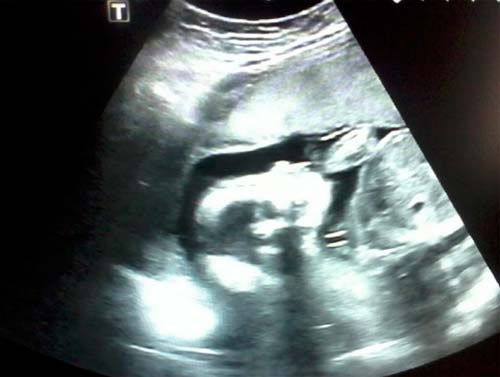

Si vous n'avez pas subi d'échographie au cours du deuxième trimestre, il sera nommé. Un médecin spécialiste vérifiera les principales dimensions du corps et des membres du fœtus, l'état des organes internes et un certain nombre d'autres indicateurs. Le placenta ne sera pas moins examiné en profondeur.

Photo échographique à 21 semaines (cliquez pour agrandir):

Avec un emplacement réussi du fœtus, vous pouvez découvrir le sexe du bébé. Mais le futur garçon ou fille peut parfois «se cacher» jusqu'à la naissance même.